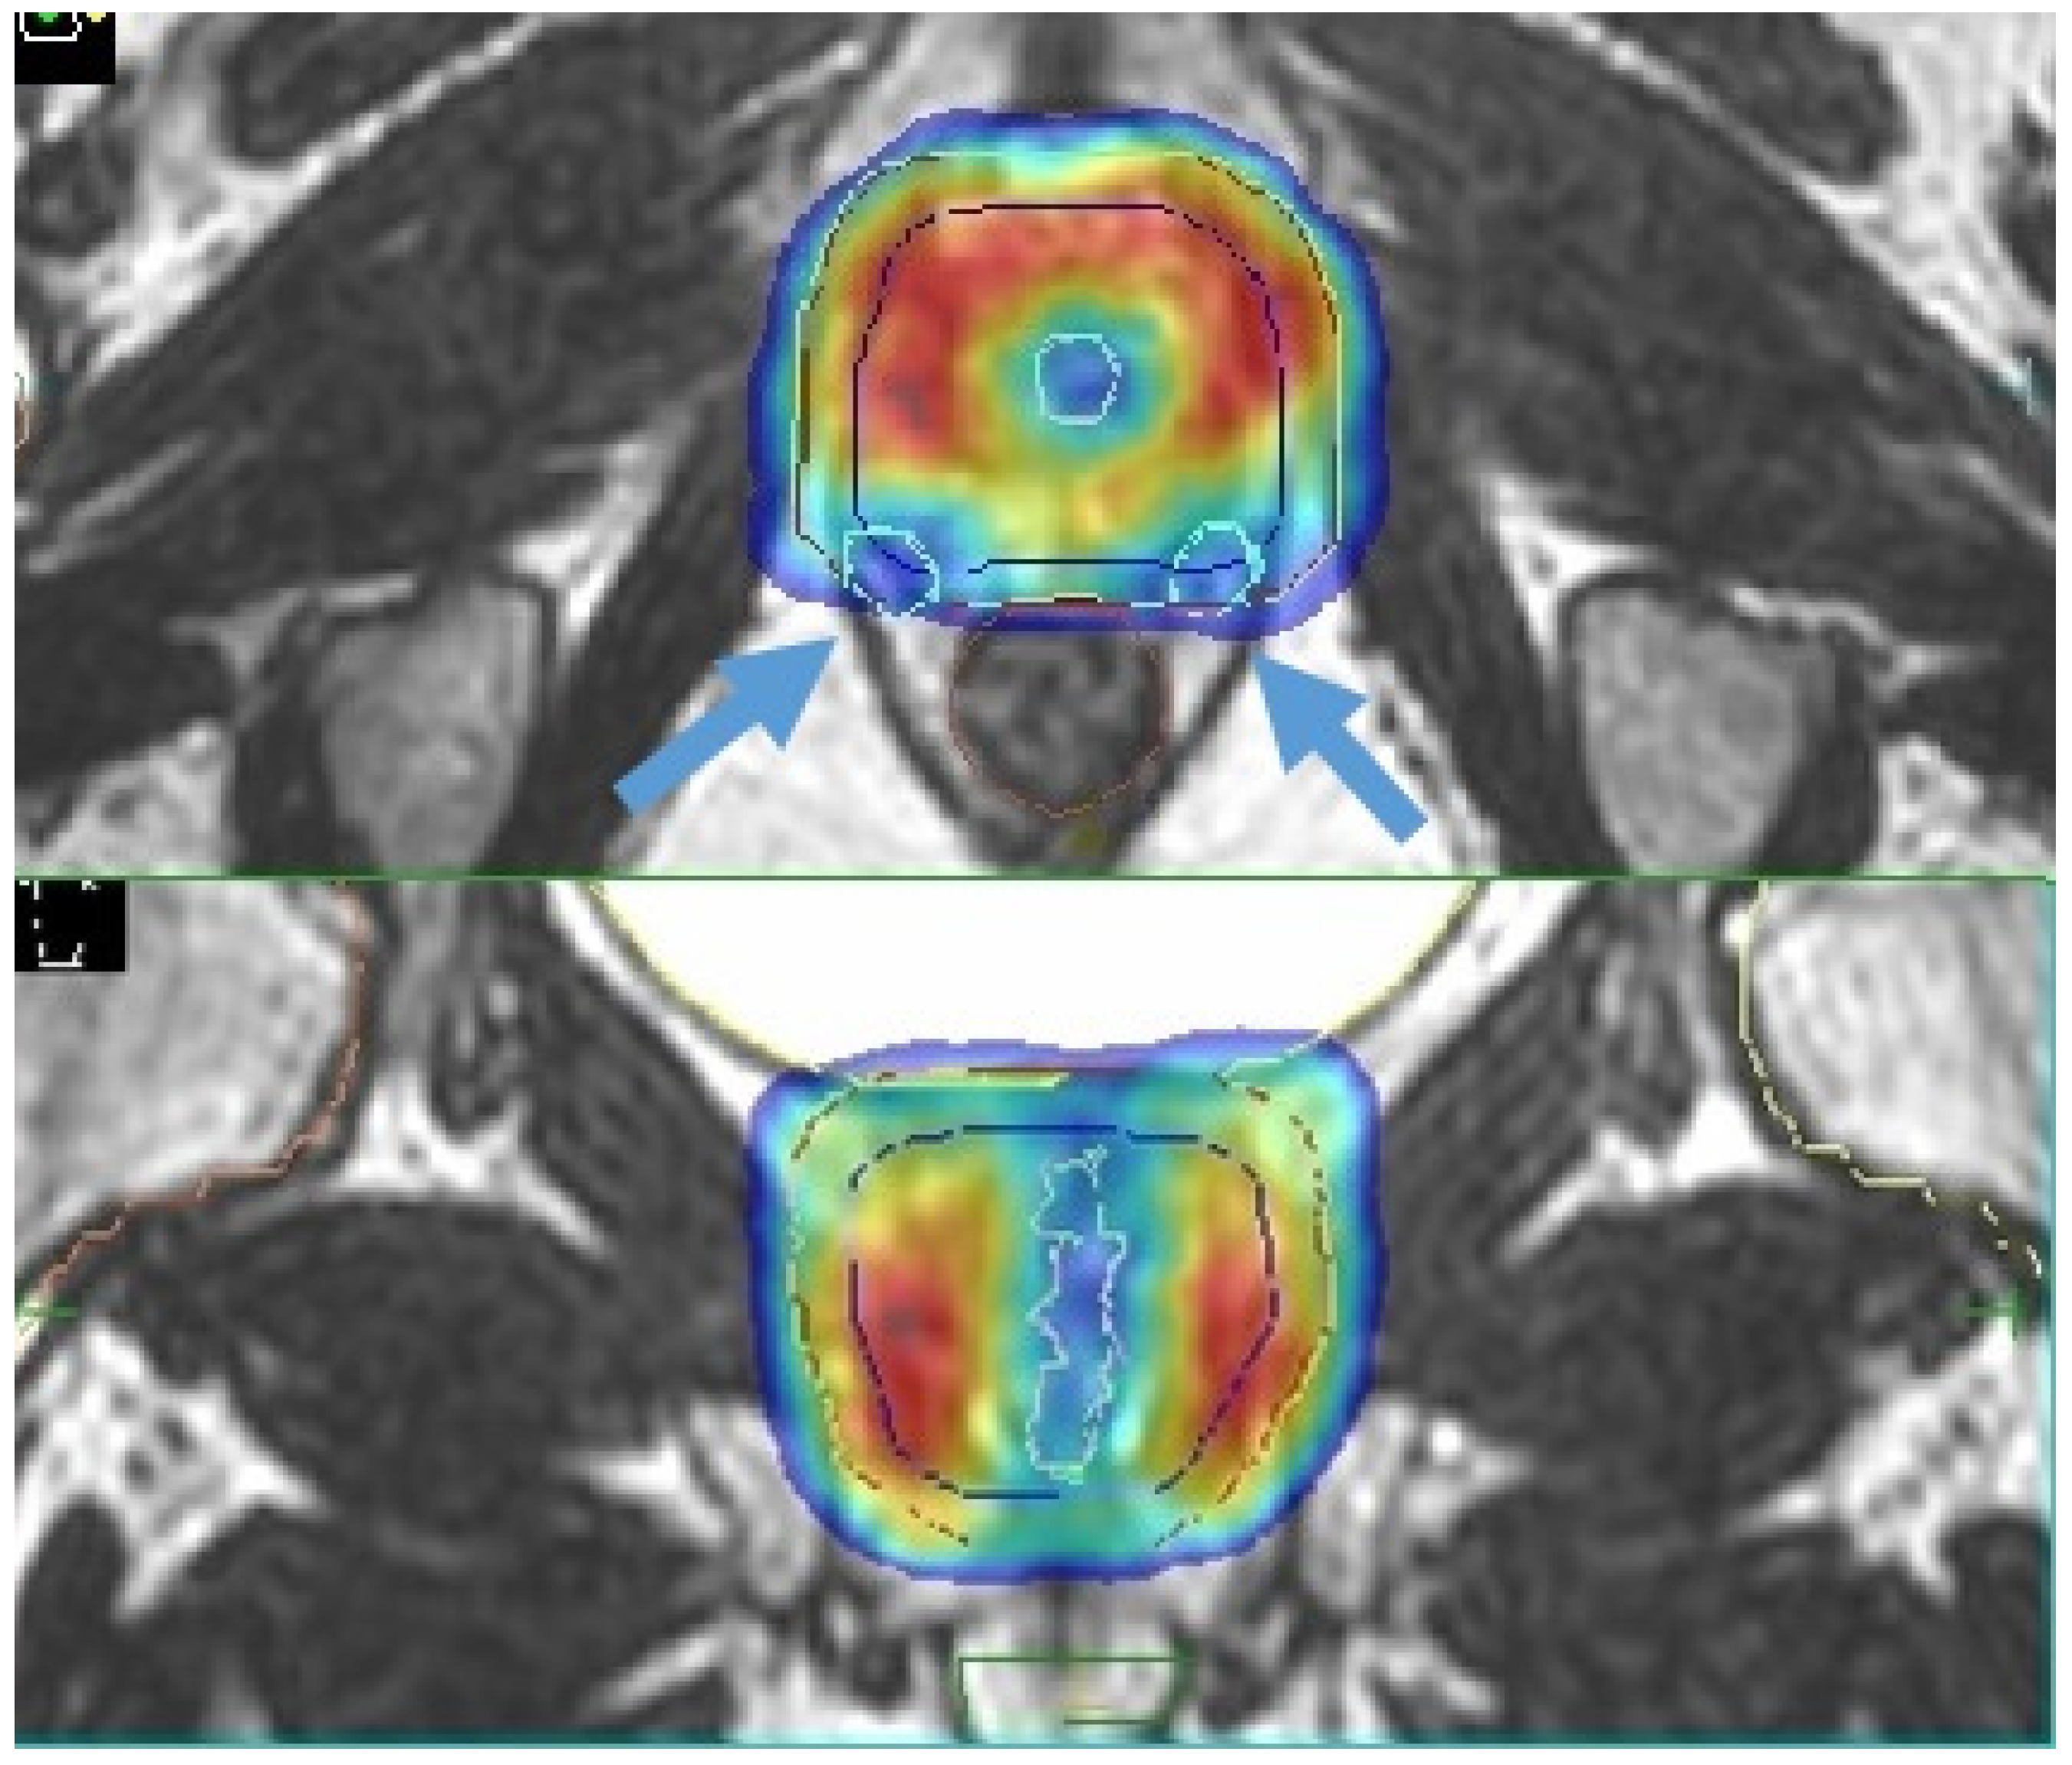

- Nicosia, L.; Sicignano, G.; Rigo, M.; Figlia, V.; Cuccia, F.; De Simone, A.; Giaj-Levra, N.; Mazzola, R.; Naccarato, S.; Ricchetti, F.; et al. Daily dosimetric variation between image-guided volumetric modulated arc radiotherapy and MR-guided daily adaptive radiotherapy for prostate cancer stereotactic body radiotherapy. Acta Oncol. 2021, 60, 215–221. [Google Scholar] [CrossRef] [PubMed]

| Nicosia et al. [39] | 10 | Elekta Unity | 35 Gy/5 fractions | Dosimetric comparison between MR-guided SBRT and conventional Linacs SBRT | MR-guided SBRT resulted in lower constraint violation rates |

- Ruggieri, R.; Rigo, M.; Naccarato, S.; Gurrera, D.; Figlia, V.; Mazzola, R.; Ricchetti, F.; Nicosia, L.; Giaj-Levra, N.; Cuccia, F.; et al. Adaptive SBRT by 1.5 T MR-linac for prostate cancer: On the accuracy of dose delivery in view of the prolonged session time. Phys. Med. 2020, 80, 34–41. [Google Scholar] [CrossRef] [PubMed]